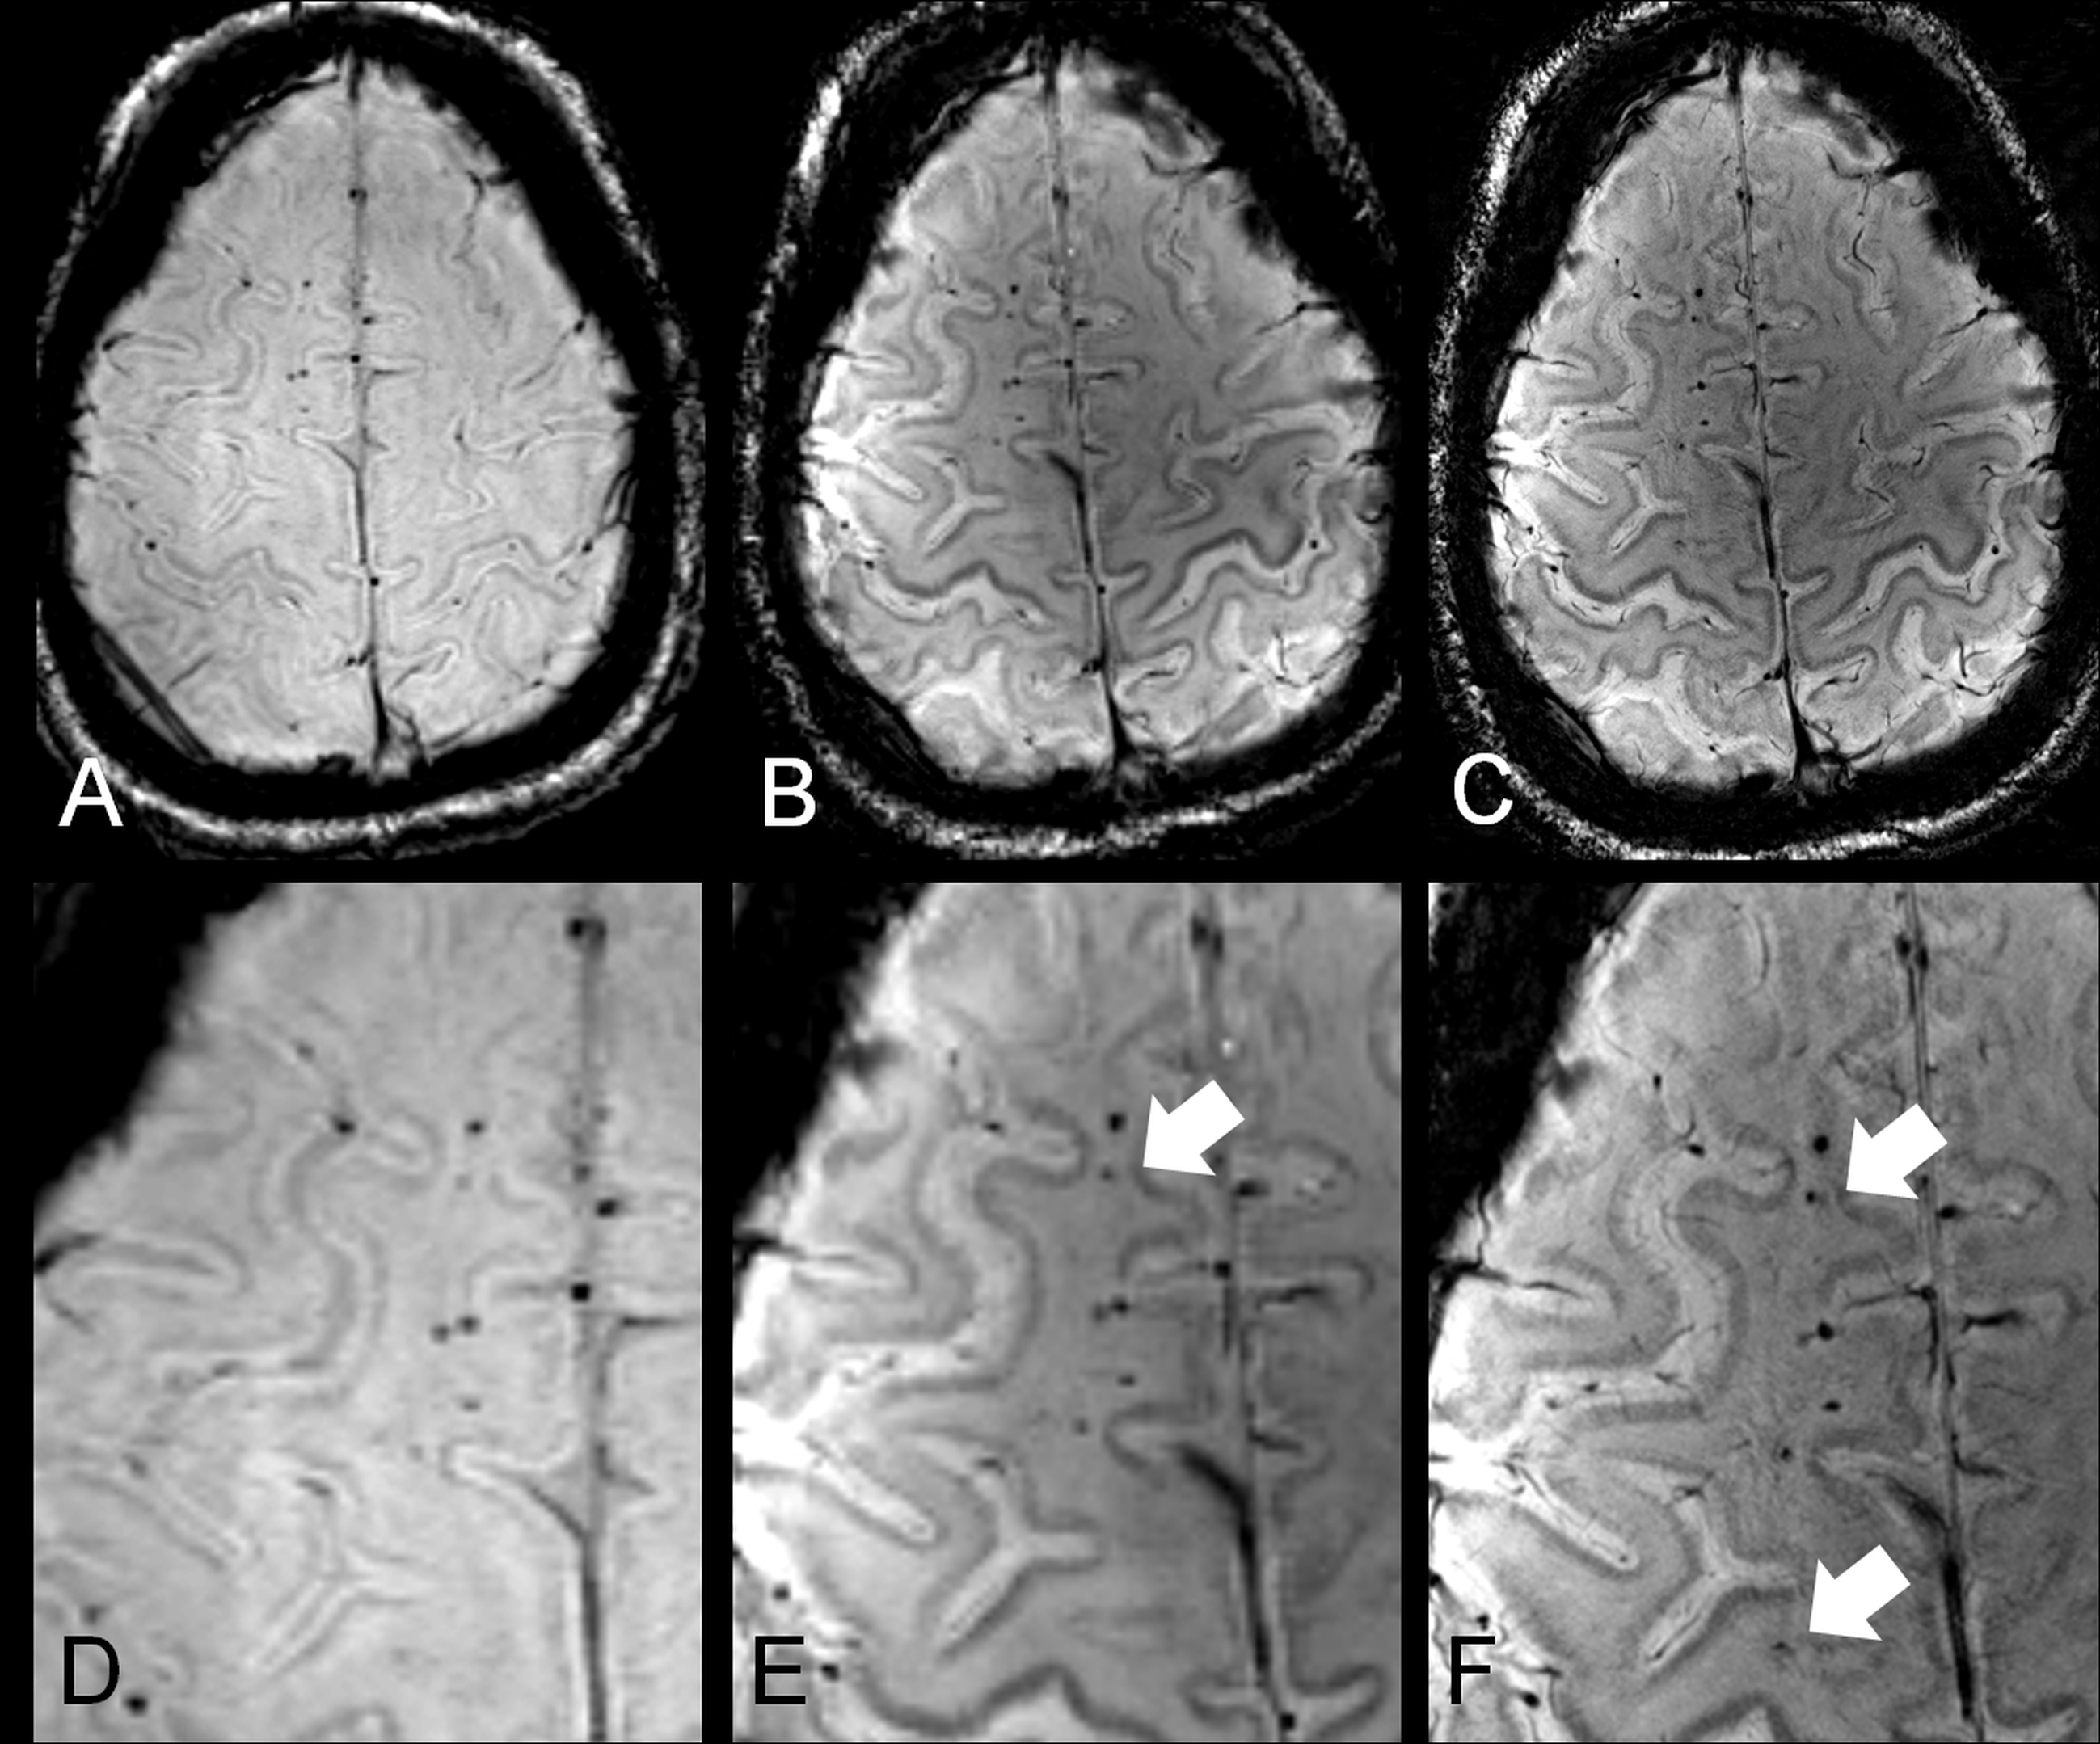

Ein Foto zu dieser Pressemitteilung (Bildbeschreibung: MRT-Aufnahmen der Scherverletzungen (Fotonachweis: UDE) Als typisches radiologisches Kennzeichen für axonale Scherverletzungen sind die Mikroblutungen als kettenartig angeordnete Signalauslöschungen im frontalen Hirngewebe erkennbar. Sie erscheinen bei 7 T (mittleres Bild) größer als bei 3 T (linkes Bild) und nach Erhöhung der räumlichen Auflösung (high resolution) werden bei 7 T zusätzliche Mikroblutungen sichtbar (rechtes Bild, Pfeile).) können Sie herunterladen unter:

Untersucht wurden zehn Probanden mit bekannten Scherverletzungen im Alter von 20 bis 74 Jahren. Die 7 T MRT stellte bei den Betroffenen signifikant mehr traumatische Mikroblutungen in der Hirnsubstanz dar als vergleichbare 3 Tesla-Aufnahmen. Dies führen die Forscher darauf zurück, dass der sogenannte Suszeptibilitätseffekt der Blutabbauprodukte, also ihre Magnetisierbarkeit, mit steigender Magnetfeldstärke zunimmt. Zudem erlaubt die 7 T MRT Aufnahmen des Gehirns in höherer räumlicher Auflösung als es mit klinisch gebräuchlichen MRT-Scannern von 1,5 T und 3 T Magnetfeldstärke möglich ist.